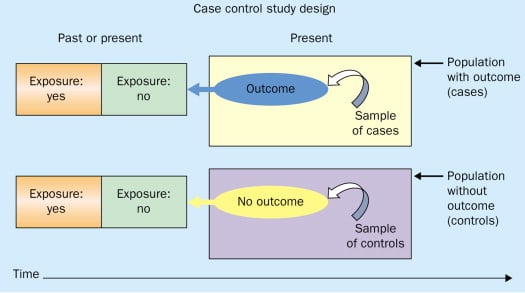

A case-control study is an experimental design that compares a group of participants possessing a condition of interest to a very similar group lacking that condition. Here, the participants possessing the attribute of study, such as a disease, are called the “case,” and those without it are the “control.”

A case-control study is a research method where two groups of people are compared – those with the condition (cases) and those without (controls). By looking at their past, researchers try to identify what factors might have contributed to the condition in the ‘case’ group.

Explanation

A case-control study looks at people who already have a certain condition (cases) and people who don’t (controls). By comparing these two groups, researchers try to figure out what might have caused the condition. They look into the past to find clues, like habits or experiences, that are different between the two groups.

The “cases” are the individuals with the disease or condition under study, and the “controls” are similar individuals without the disease or condition of interest.

Researchers will first identify the two groups, and then look back in time to investigate which subjects in each group were exposed to the condition.

If the exposure is found more commonly in the cases than the controls, the researcher can hypothesize that the exposure may be linked to the outcome of interest.

Figure: Schematic diagram of case-control study design. Kenneth F. Schulz and David A. Grimes (2002) Case-control studies: research in reverse . The Lancet Volume 359, Issue 9304, 431 – 434

A case control study is a retrospective, observational study that compares two existing groups. Researchers form these groups based on the existence of a condition in the case group and the lack of that condition in the control group. They evaluate the differences in the histories between these two groups looking for factors that might cause a disease.

By evaluating differences in exposure to risk factors between the case and control groups, researchers can learn which factors are associated with the medical condition.

Case-control studies are observational studies because researchers do not control the risk factors—they only observe them. They are retrospective studies because the scientists create the case and control groups after the outcomes for the subjects (e.g., disease vs. no disease) are known.